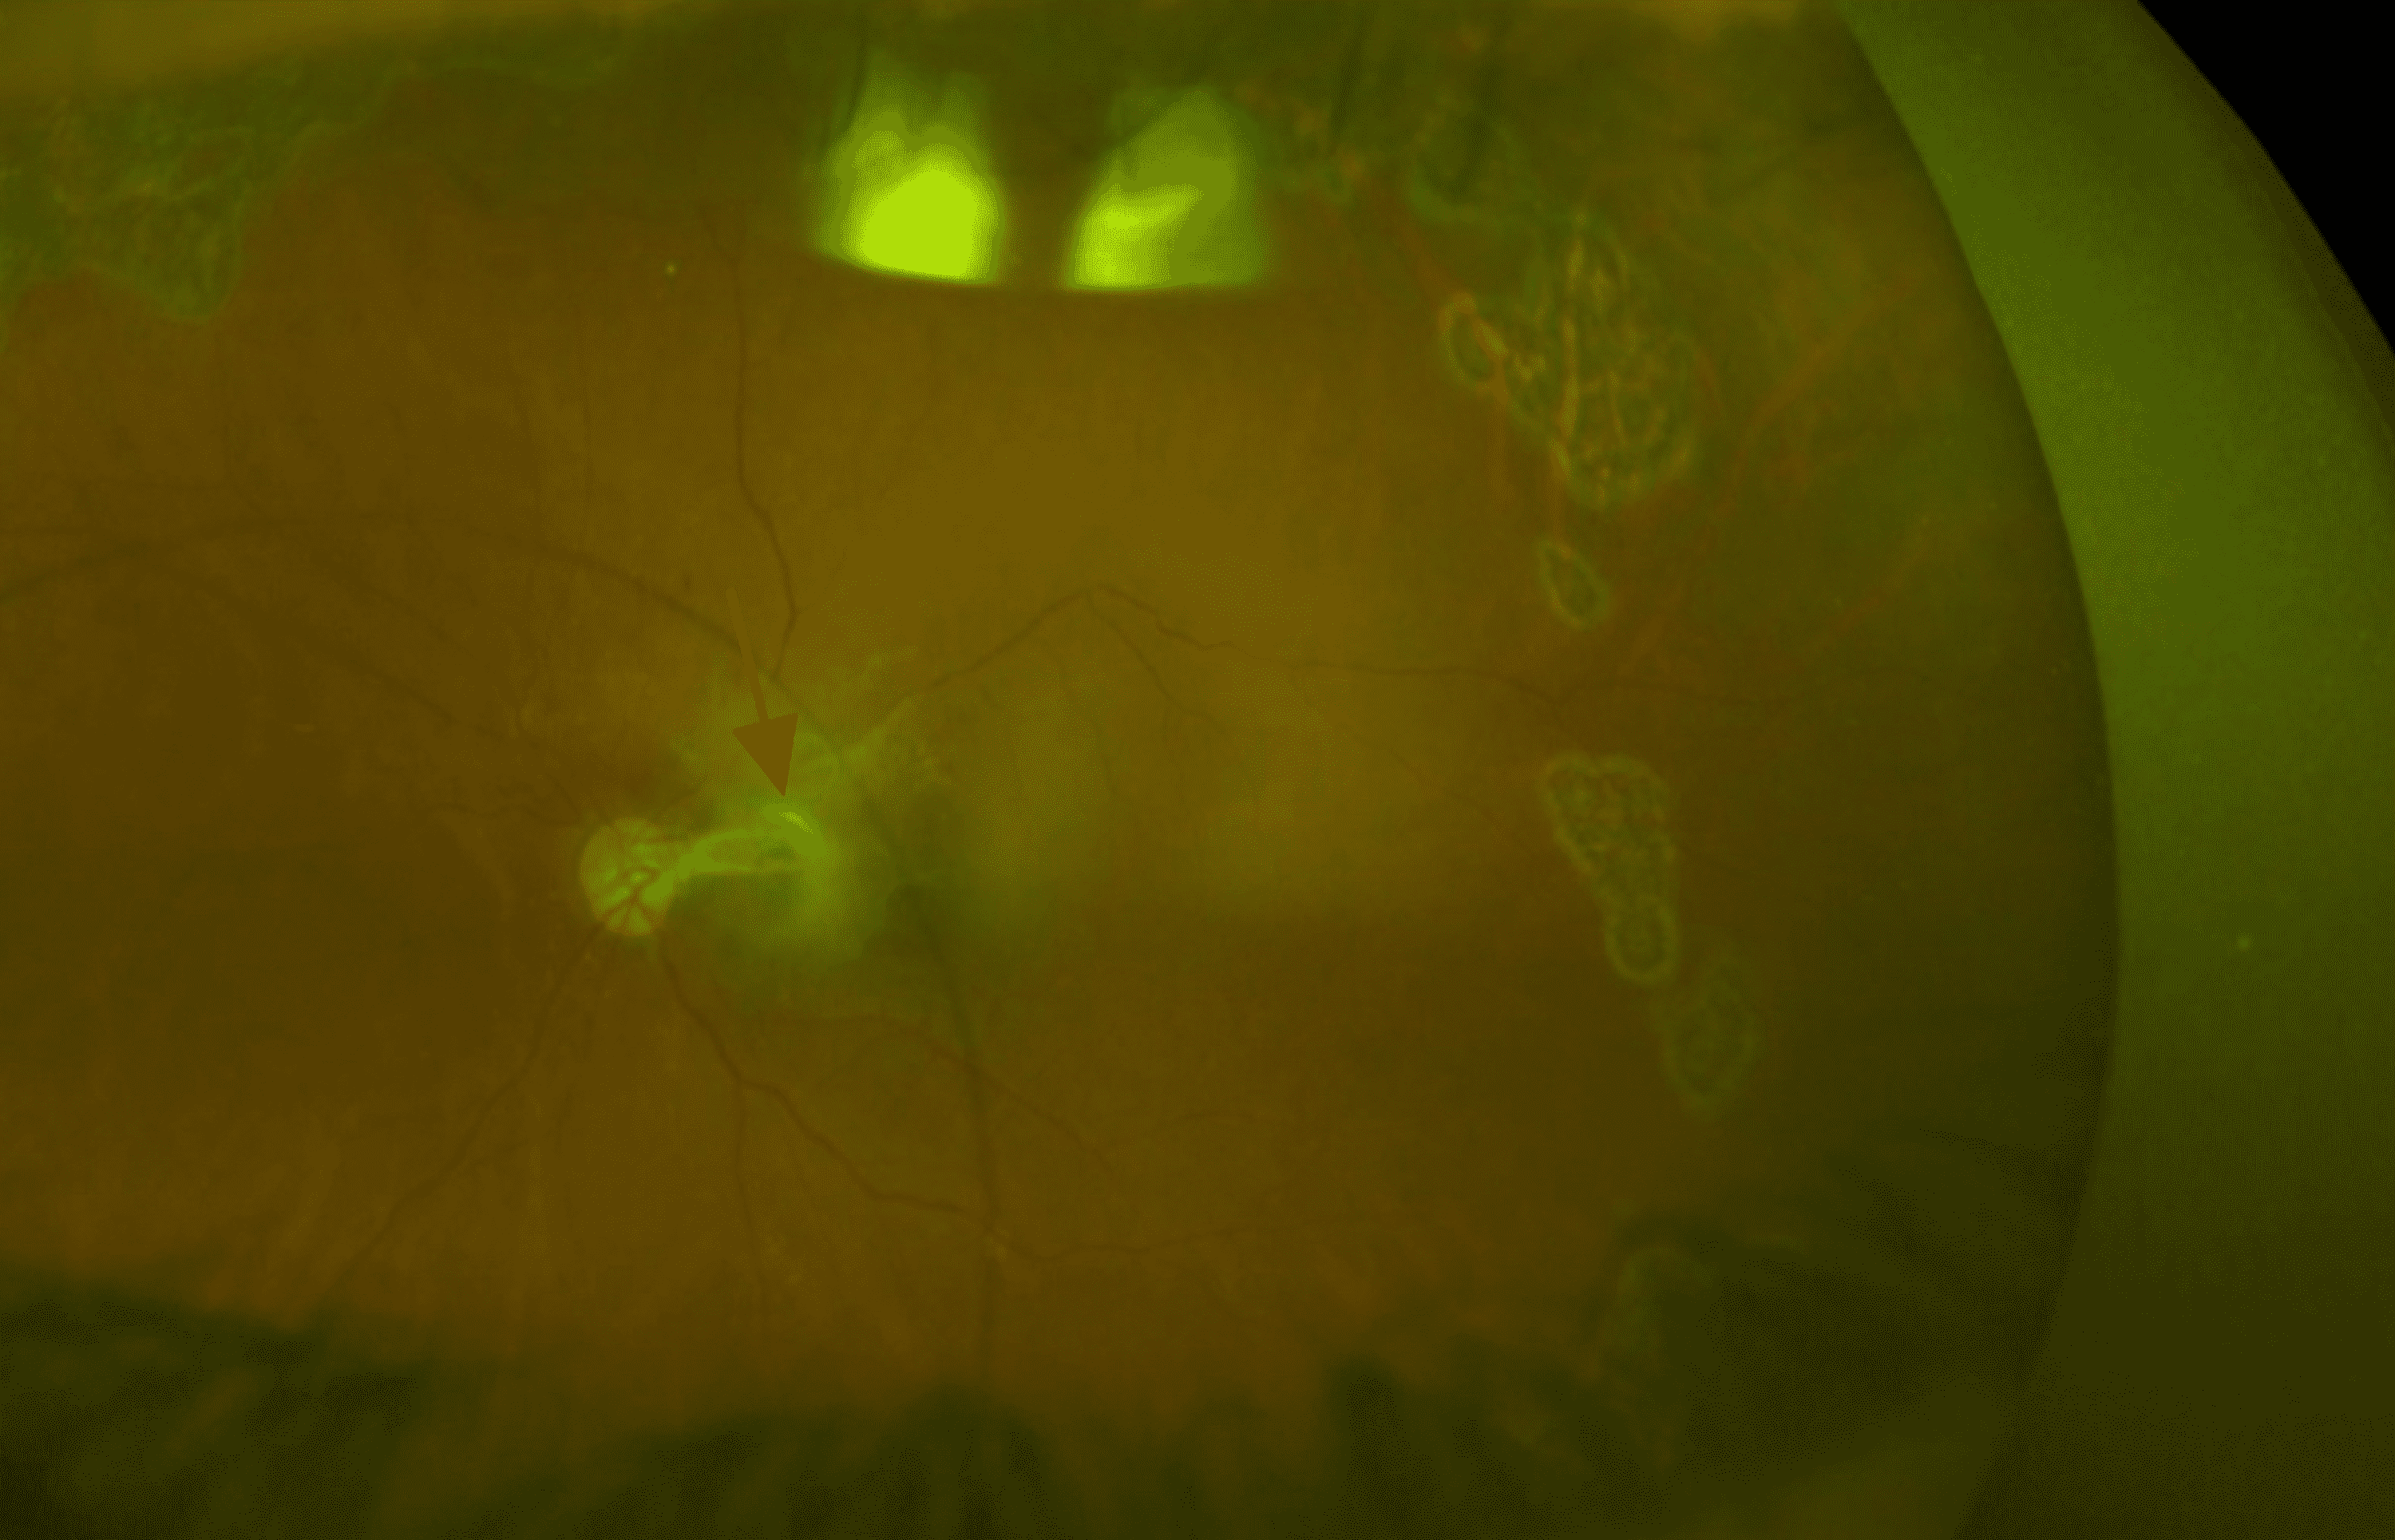

From www.eyerounds.org

Ch 3 The Eye. A Patient's Guide to Optic Nerve Eye Hemorrhage the authors reviewed 93 consecutive cases with optic disc swelling (ods) to compare clinical manifestations. The retinal nerve fiber layer (rnfl) is the group of nerve cells that. disc hemorrhage is identified on examination of the optic nerve and/or on color fundus photographs. Exclusion criteria included subjects with hemorrhages in association with diabetic and hypertensive retinopathy, ischemic optic. Optic Nerve Eye Hemorrhage.